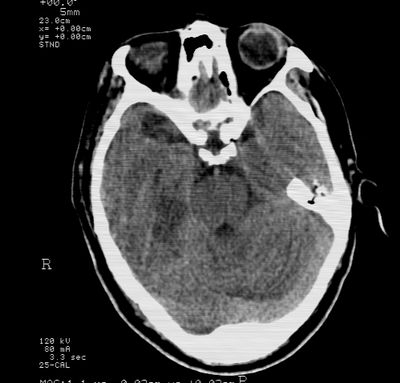

标题: CT21793:李x,男,62岁,头疼,头晕,家属否认有出血病史, [打印本页]

标题: CT21793:李x,男,62岁,头疼,头晕,家属否认有出血病史,

右枕叶.右侧脑室前角旁脑梗塞

右基底节,海马并侵及右枕,左枕叶梗塞

右枕叶.右侧脑室前角旁脑梗塞。

支持多发脑梗塞

支持右基底节,海马并侵及右枕,左枕叶梗塞。

支持右基底节,海马并侵及右枕,左枕叶梗塞。建议增强。

支持右基底节,海马并侵及右枕,左枕叶梗塞

多发性梗塞

多发梗塞,左小脑软化灶

支持多发脑梗塞!

多发性脑梗塞。

考虑多发脑梗塞,建议mri检查。